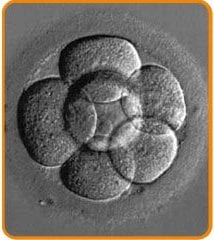

The next step of embryonic development is its division into cells called blastomeres. Embryos are evaluated daily for the number, size, shape of blastomeres, and the existence or not of fragments.

The second and third day after the egg collection they usually consist of 4 and 8 blastomeres respectively. The embryos are usually transferred on the second or third day.